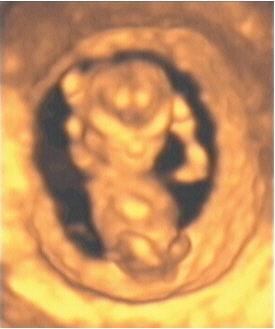

![]() |

| Figure 18, a 3-D ultrasound image of a fetus at 12 weeks gestation. Image courtesy of Stefano Ciatti, M.D. |